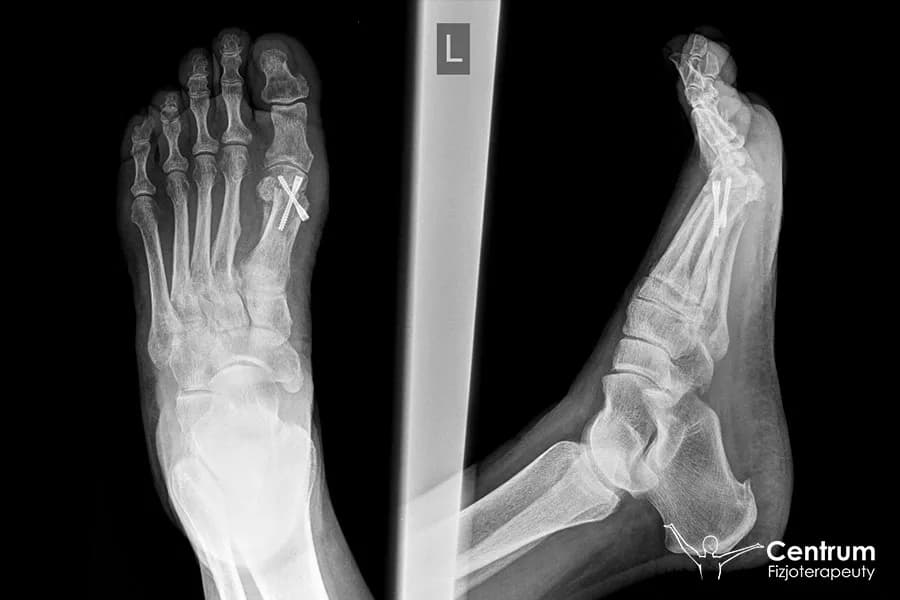

Wybór metody operacyjnej ma bezpośredni wpływ zarówno na długość samego zabiegu, jak i na przebieg rekonwalescencji. W Polsce stosujemy wiele technik, a do najpopularniejszych należą metody Scarf, Chevron, Akin, Lapidus. Każda z nich ma swoje wskazania i specyfikę. Na przykład, techniki takie jak Scarf czy Chevron, polegające na osteotomii (przecięciu kości) i stabilizacji śrubami, mogą trwać nieco dłużej ze względu na precyzję cięć i mocowania. Coraz większą popularność zdobywa metoda MICA (Minimal Invasive Chevron Akin), czyli technika przezskórna. Jest ona małoinwazyjna, co często przekłada się na krótszy czas operacji i, co ważne dla pacjenta, potencjalnie szybszy powrót do sprawności, choć nie zawsze jest to regułą i zależy od indywidualnego przypadku.

Po około 6 tygodniach od operacji, po kontroli lekarskiej i wykonaniu kontrolnego zdjęcia RTG, które potwierdzi prawidłowe zrosty kostne, zazwyczaj możliwe jest pełne obciążanie stopy i stopniowe odstawienie kul. To bardzo wyczekiwany moment dla pacjentów! Pamiętaj jednak, że nawet po odstawieniu kul, stopa może być wciąż nieco obrzęknięta. Obrzęk po operacji haluksa jest zjawiskiem naturalnym i może utrzymywać się nawet do 4-5 miesięcy, stopniowo ustępując. Ważne jest, aby nadal dbać o stopę i kontynuować zaleconą fizjoterapię.